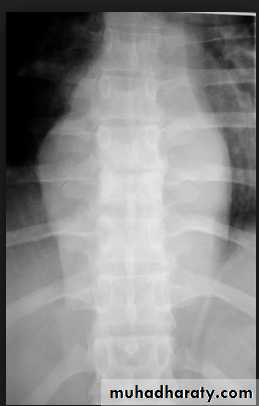

The plain film shows features which are typical for spinal tuberculous disease.

There is an extensive paraspinal soft-tissue mass.Detail in the underlying spine is poor but there is early crowding of ribs posteriorly, indicating early vertebral collapse.

(B) Coronal MR image of the thoracic spine demonstrates destruction of the intervertebral disc at the point where the paraspinal widening is maximal and this change is associated with alteration of signal from the vertebrae.